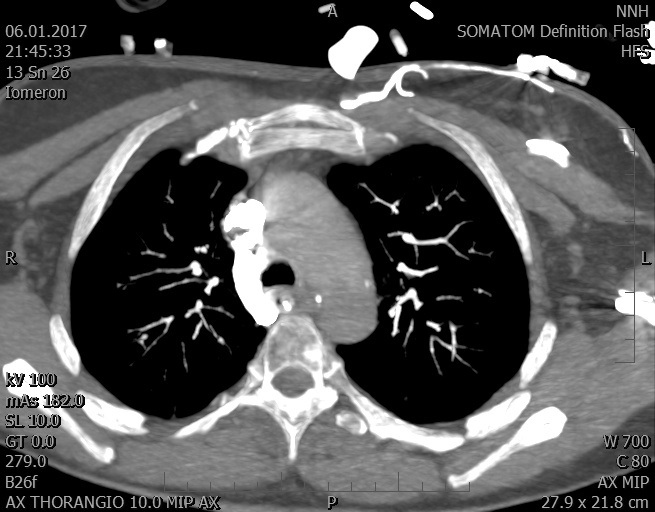

Video 2 - Echokardiograficky byla zjištěna těžká dysfunkce dilatační levé komory s nezvětšenou pravou komorou.Pro nejasnou příčinu zástavy jsme provedli i vyšetření výpočetní tomografií (CT), které vyloučilo plicní embolizaci (série 1 - soubory na konci článku). V den přijetí při přetrvávající oběhové nestabilitě byla nemocná opakovaně defibrilována pro fibrilaci komor se stabilizací rytmu po podání amiodaronu a mesocainu. Dle hemodynamických měření se jednalo o těžký kombinovaný šok. Vstupní laboratorní vyšetření bylo bez větších pozoruhodností. Posléze jsme doplnili anamnézu od příbuzných a zjistili, že pacientka užila do dvou hodin před srdeční zástavou první tabletu amoxicilinu na lehký respirační infekt. Při nevýtěžnosti vstupních vyšetření a nových anamnestických informacích jsme doplnili 14 hodin po kolapsu vyšetření koncentrace tryptázy v séru, která byla extrémně zvýšena (tabulka 2), což nás vedlo k podezření na anafylaxi.